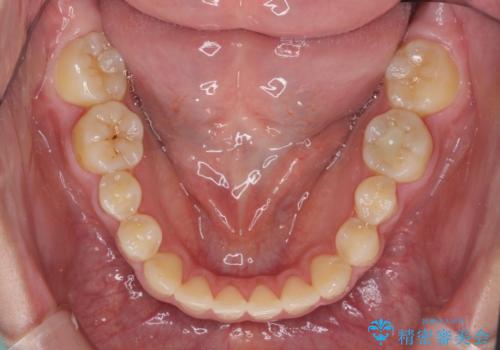

- 前歯のオープンバイトを気にして来院された患者様です。

上下前歯の前後位置が大きくずれていたため、上顎左右第一小臼歯2本を抜歯してワイヤー装置による矯正治療を行うこととしました。

オープンバイトの原因は舌の突出癖であり、癖が改善されないと治療経過に影響を及ぼすため、舌のトレーニングを指示しました。

なかなか癖が改善されず、トレーニングも断続的に行ったため、治療期間は長期化しました。